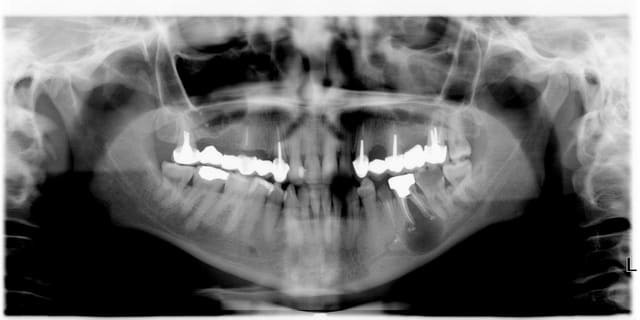

Observez le magnifique bridge secteur I fait en 2006 de 18 à 13 avec comme piliers...

... 18 et 13 :)

Et une jolie racine de 15 laissée "en jachère".